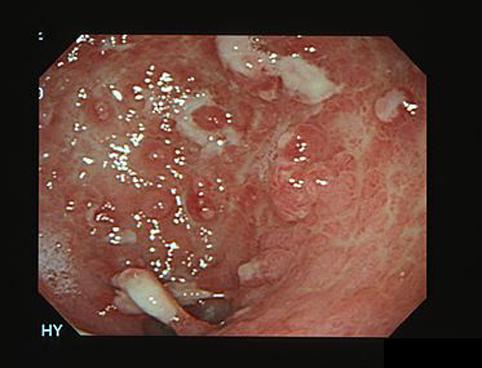

질환(병리주체)의 분류 악성 림프계종양/악성 림프종

부위(장기별) 위(부위)/전정

검사방법 내시경

종양의 육안분류 0형(표재형)/IIc형(IIc)

종양의 최대경(밀리미터) 40이상

종양의 심달도 sm